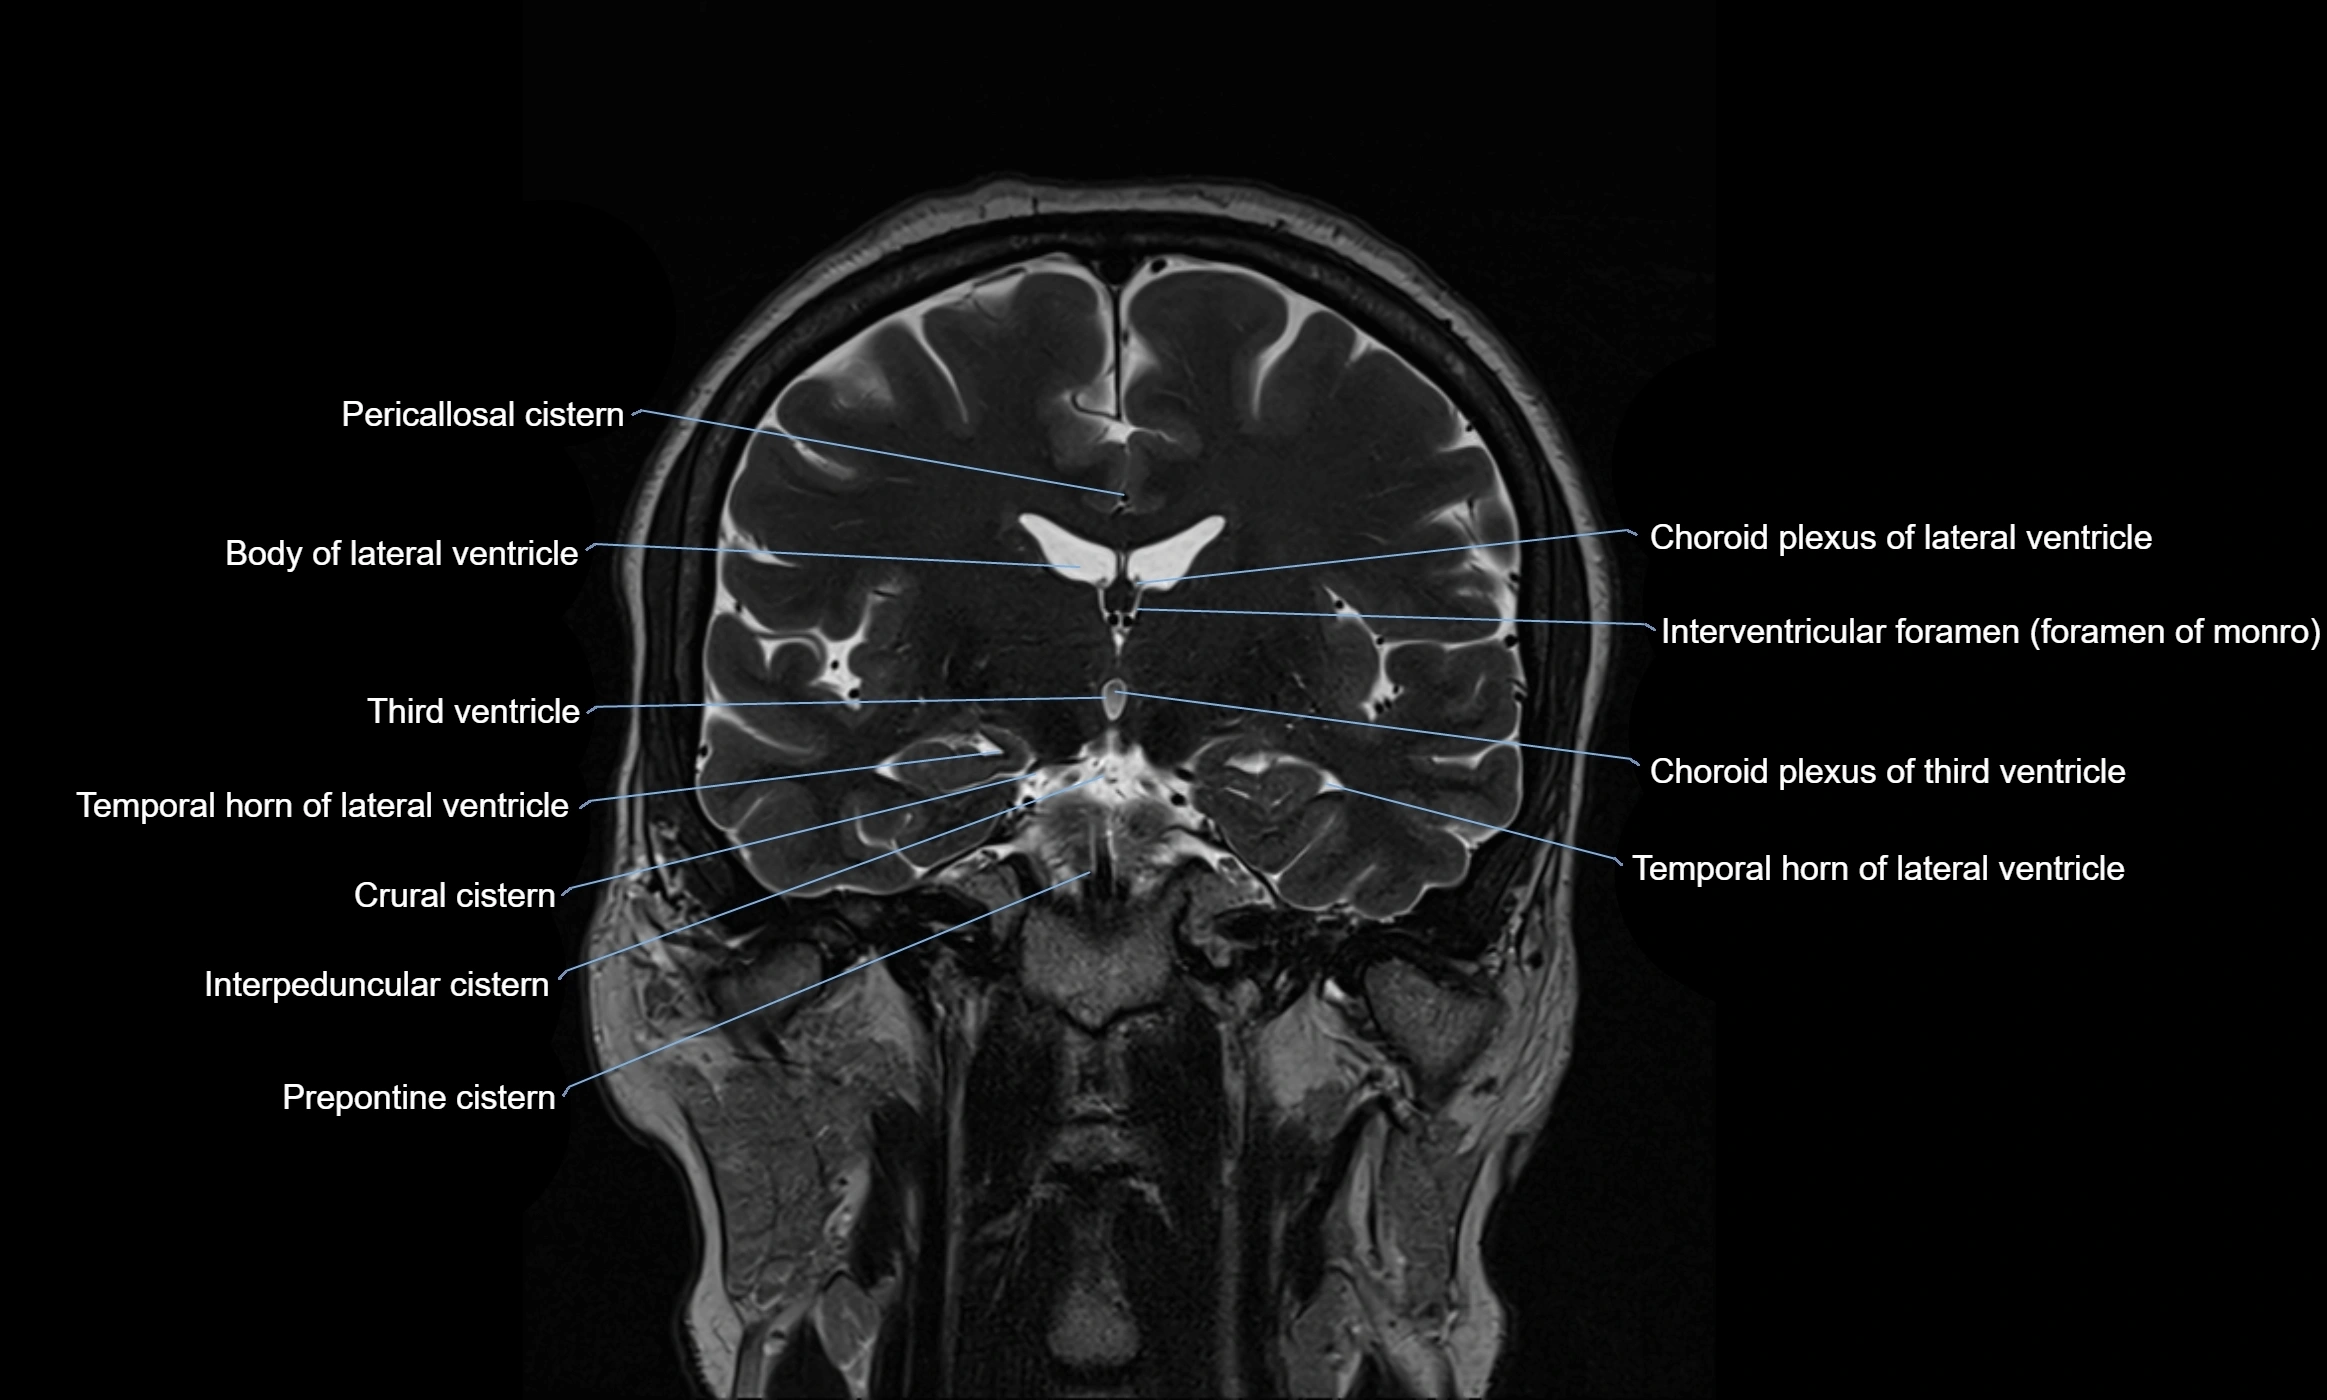

MRI images

image